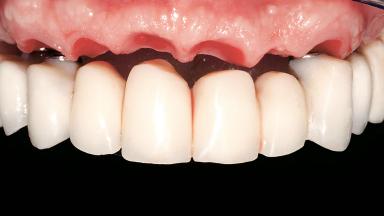

Immediate Loading of Six Implants in the Maxilla and Final Restoration with a Full-Arch CAD/CAM Zirconia FDP

Prosthesis Type FDP

Defining Characteristics Fully edentulous upper jaw to be rehabilitated with an implant-borne fixed dental prosthesis